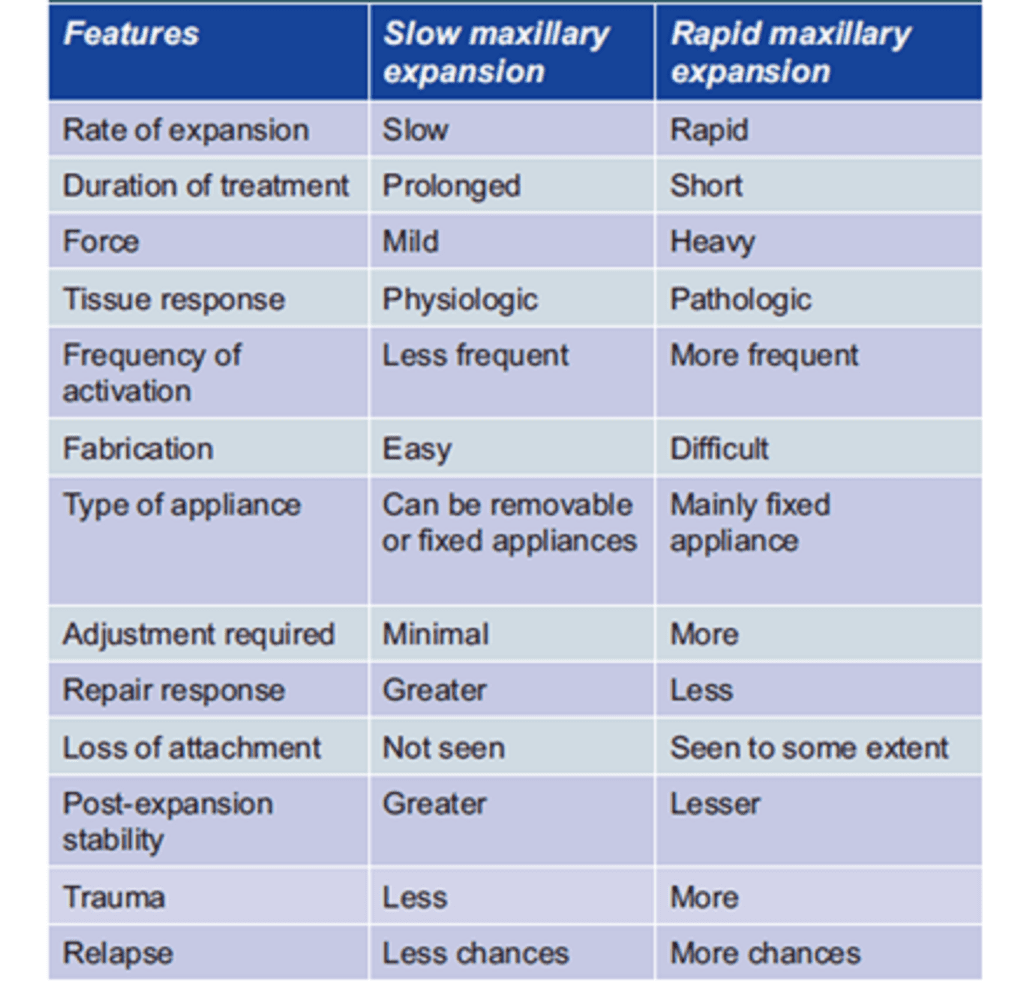

Comparison of effects of slow and rapid palatal expansion

- When the effects of both slow and rapid maxillary expansions are compared, there is no net difference in the skeletal and dental changes produced by rapid and slow maxillary expansions.

- According to various studies, after RME 10 mm of expansion is achieved of which skeletal expansion is 8 mm and dental expansion is 2 mm.

- After 4 months, 10 mm of the dental expansion is still present and only 5 mm of skeletal expansion is present. Hence, there is 5 mm of skeletal expansion and the remaining 5 mm account for dental movement.

- With slow maxillary expansion, after a 10-week period of expansion, the same amount of 5 mm of skeletal and dental expansion is produced.

- In rapid expansion, there is more skeletal relapse due to delay in the bone fill in the mid-palatal region after rapid expansion during which the relapse of the skeletal expansion occurs, whereas in slow maxillary expansion, the rate of expansion is close to the maximum rate of bone fill (physiological expansion).